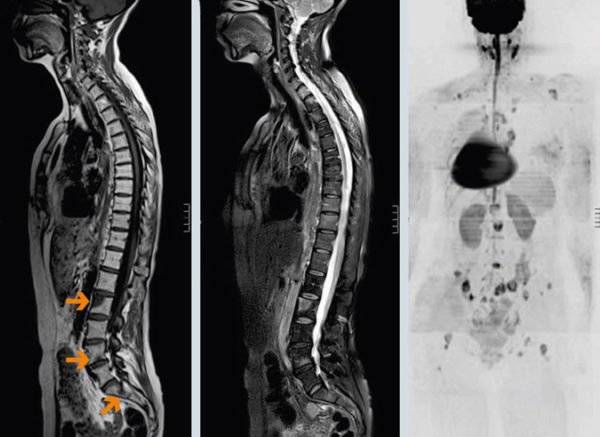

КТ и МРТ

Если сравнивать УЗИ с другими передовыми технологиями – КТ и МРТ, здесь тоже имеются отличия. Хоть по способу исследования (технологически) это новые методы, но они не настолько информативны, как ультразвук. Основаны компьютерные исследовательские методики на магнитном резонансе, и с их помощью можно оценивать состояние околопозвоночных тканей, дисков – преимущественно костной структуры. Состояние внутренних органов гораздо яснее может представить ультразвуковое изображение.

МРТ позвоночника